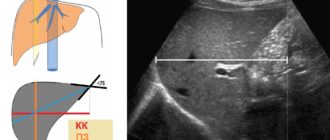

УЗИ ГЕПАТОМЕГАЛИЯ ПРАВАЯ ДОЛЯ 162 ЛЕВАЯ 80

Диффузные изменения печени и поджелудочной(Гепатомегалия) — что это такое? Ставим лайки и подписываемся на